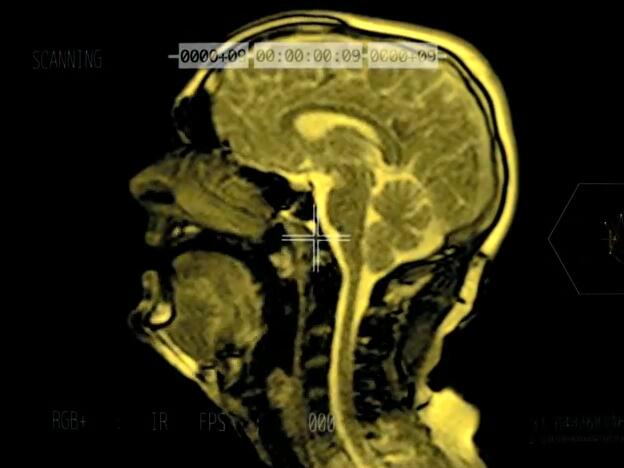

За заснемането му музикантът прекарва близо три часа пеейки в легнало положение в машина за ядрено-магнитен резонанс. Благодарение на това, можем да видим какво се случва в главата и най-вече – в устния апарат на един човек, докато пее.